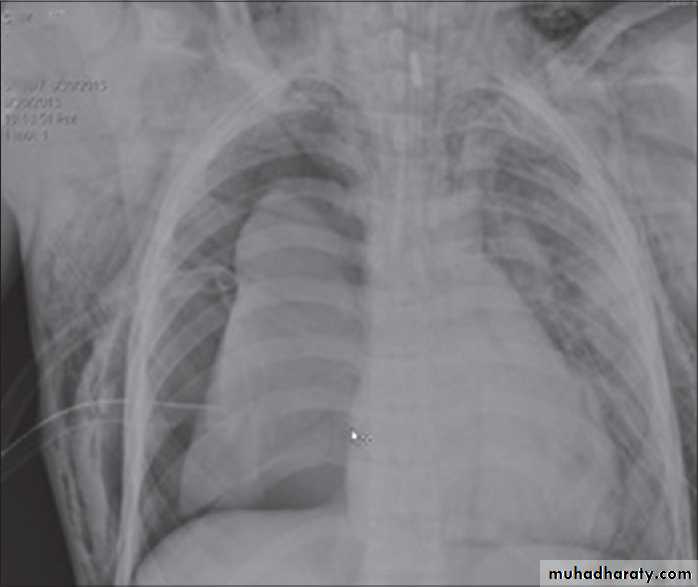

History; too shy to take of his shirt in the pool!